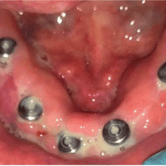

Edentulismo completo

El edentulismo completo es la ausencia total de dientes en una o ambas arcadas.

Los pacientes tienen dificultad para masticar, hablar y pueden sentirse incómodos con su apariencia.

El tratamiento puede incluir la colocación de una prótesis completa sobre implantes, proporcionando una solución fija y estable